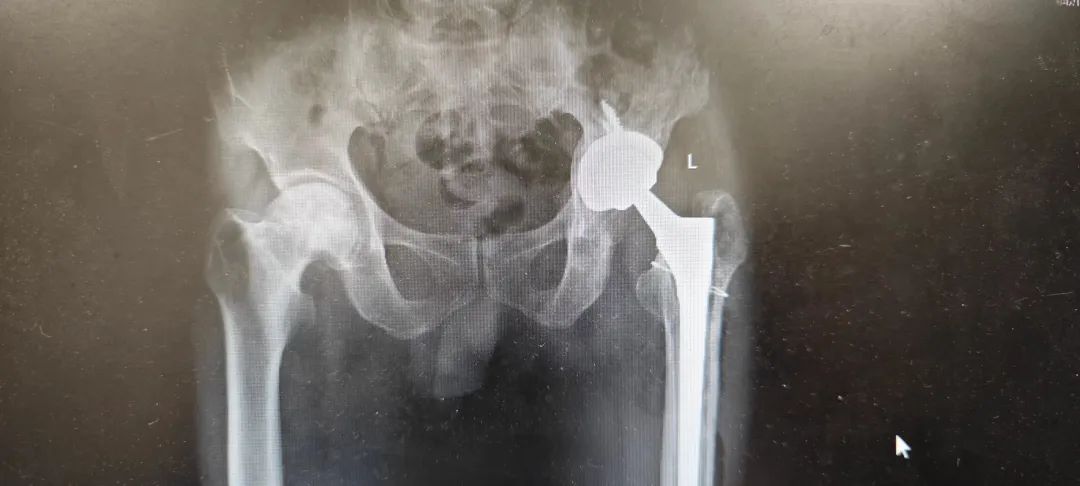

該患者因“左全髖關(guān)節(jié)置換術(shù)后2年,疼痛及關(guān)節(jié)不穩(wěn)10天”入院。兩年前在當(dāng)?shù)蒯t(yī)院行全髖關(guān)節(jié)置換術(shù)治療,10天余前出現(xiàn)左髖部不穩(wěn)等情況,后逐漸加重,輾轉(zhuǎn)來我院關(guān)節(jié)外科就診治療,門診檢查發(fā)現(xiàn)髖臼側(cè)及股骨側(cè)關(guān)節(jié)假體均存在松動不穩(wěn)情況,嚴重影響活動及生活質(zhì)量,經(jīng)檢查后門診以“左全髖關(guān)節(jié)置換術(shù)后松動”收治入院。

圖1-術(shù)前檢查可見左全髖置換側(cè)假體明顯松動旋轉(zhuǎn)不穩(wěn)